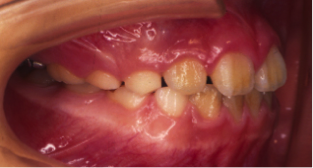

叢生(そうせい)

20歳/女性

悩み:歯がデコボコ

八重歯が押し出されて歯がでこぼこに並んでいる状態

治療期間:約2年4ヶ月

治療前

治療後

奥の歯が倒れて狭くなっている台形の歯列を広げて歯を起こす治療で、奥の歯が見えるようになるUの字型に治しました。

上の歯下の歯、それぞれ2本づつ第一小臼歯を抜歯した治療となりました。

歯を見せて笑えるようになり喜んでもらいました。